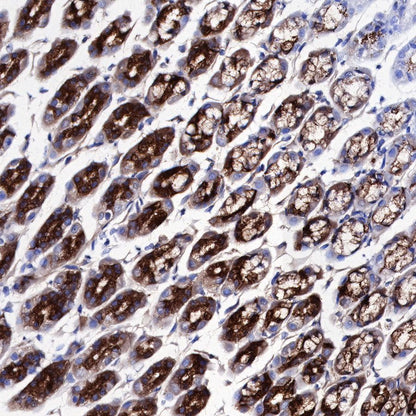

IHC shows positive staining in paraffin-embedded rat stomach. Anti-PG II/PGC antibody was used at 1/1000 dilution, followed by a HRP Polymer for Mouse & Rabbit IgG (ready to use). Counterstained with hematoxylin. Heat mediated antigen retrieval with Tris/EDTA buffer pH9.0 was performed before commencing with IHC staining protocol.